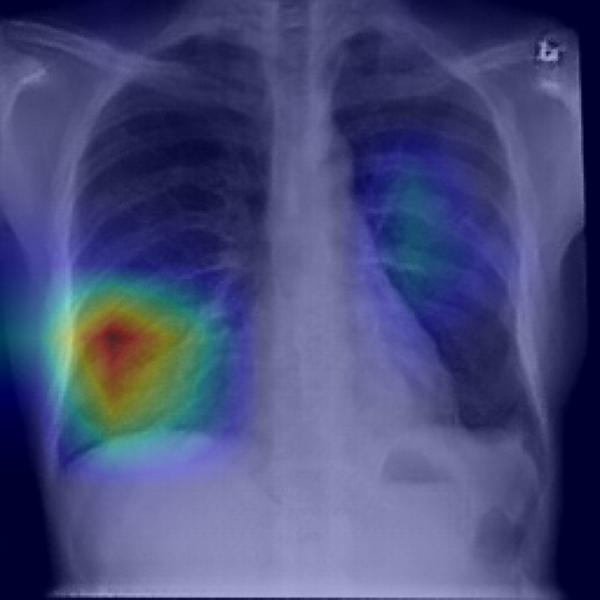

4.2.4 Grad-CAM heat activation map

Figures 33 and 34 show the two end-points ( and ) for one representative X-ray. The CNN‐based neutralizer leaves the hotspots largely intact and increases the male probability from to . In contrast, the ViT neutraliser erases the right-lung focus and tightens the left-lung patch, pushing the classifier to an almost certain male prediction (). Figure 35 presents the full -sweep for the ViT-based neutralizer, confirming that the highlighted sex evidence fades smoothly and the model’s male probability falls toward 0.5 once .